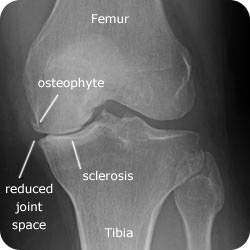

Osteoarthritis of the Knee

xr-knee-oa-ap-250-label